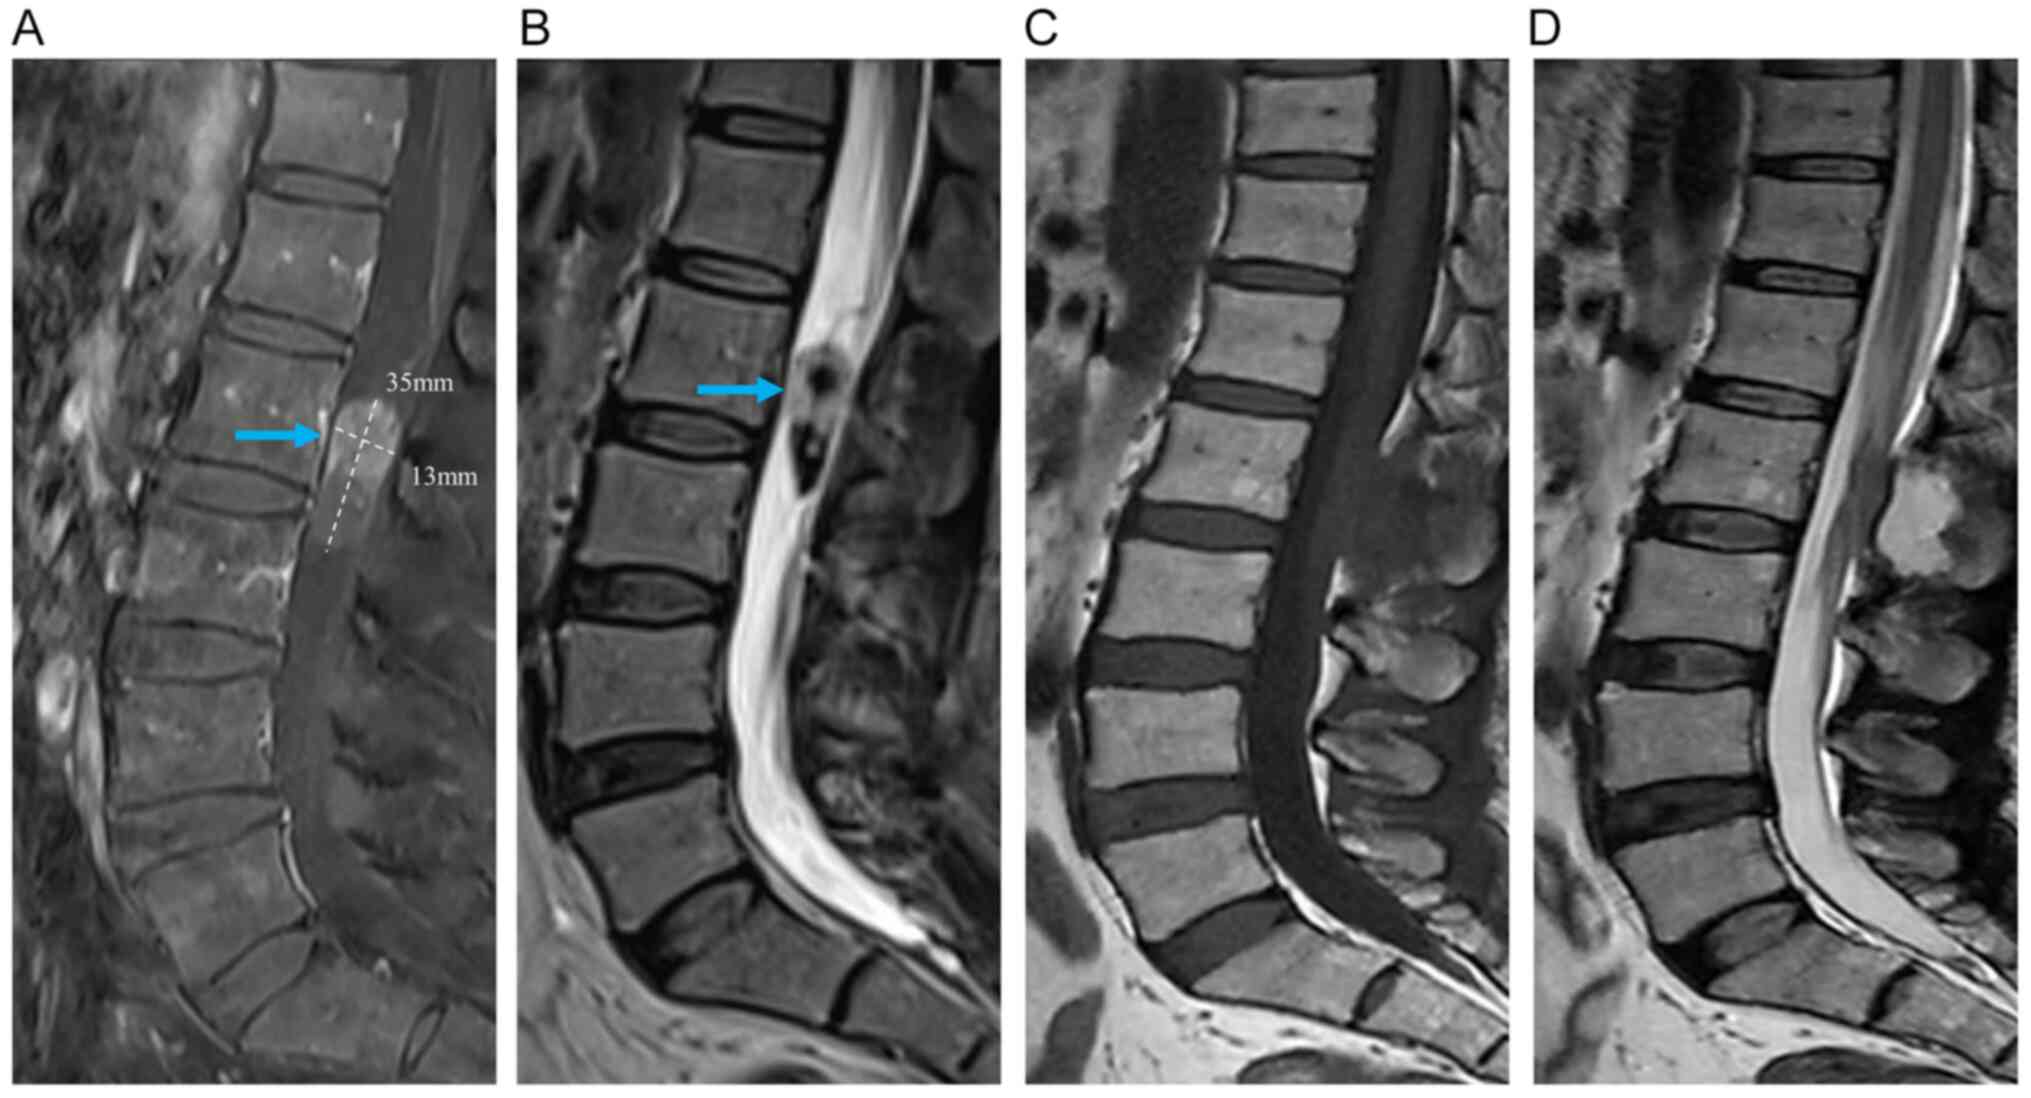

Pure endoscopic minimally invasive surgery with a non‑expandable tubular retractor for intradural extramedullary spinal tumors

Minimally invasive spinal surgery (MISS) for intradural extramedullary (IDEM) spinal tumors is a safe and effective surgical strategy. Currently, various tubular retractors are widely used in the MISS of IDEM spinal tumors, primarily relying on microscopic visualization. To the best of the authors' knowledge, there is no report of pure endoscopic surgery with parallel non‑expandable tubular retractors for IDEM spinal lesions. The present study reports a case series of IDEM spinal tumors that were treated via pure endoscopic MISS with a parallel non‑expandable tubular retractor. The extent of tumor resection was evaluated by comparing preoperative and postoperative magnetic resonance imaging (MRI). The initial and follow‑up clinical conditions were assessed according to the visual analog scale for pain and the modified McCormick scale for neurological status. Postoperative MRI demonstrated that all cases had achieved a gross total resection. After the operation, the clinical symptoms of all patients were significantly improved and there were no serious postoperative complications. At the initial follow‑up, the pain experienced by the patients was significantly reduced or had even disappeared, and the neurological deficit was improved by at least one grade on the modified McCormick scale. The present report indicates that pure endoscopic MISS with a parallel non‑expandable tubular retractor may be an effective and safe surgical strategy for IDEM spinal tumor resection.

Figure 1